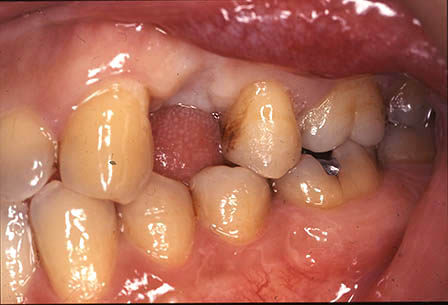

インプラントの埋入前後の口腔内写真

下顎臼歯部

最も頻繁に遭遇するケースですが、取り外しの義歯を作っても使われない場合が多く、インプラントによる固定式の義歯は快適で自分の歯と同じように咬めます。